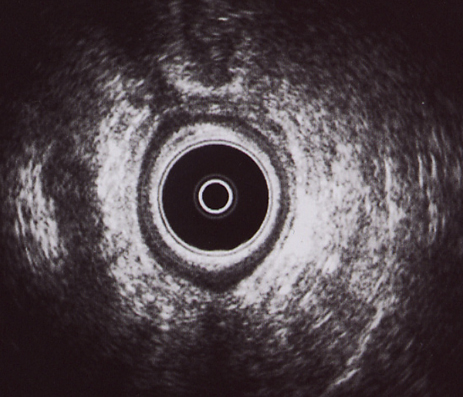

CANAL ANAL ALTO: Imagen hipoecogénica por encima de la rama derecha del puborrectal y posterior, compatible con absceso postanal y supraelevador derecho